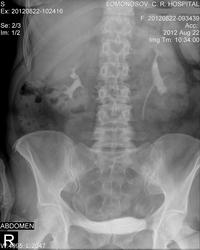

Пациентка с хроническим пиелонефритом при поступлении после узи МКБ ( частично окклюзирующий камень левого мочеточника?) на снимках у меня вызывают вопросы лоханки, да и чашечки тоже... положение справа, размер левой почки...одни сплошные сомнения помогите советом, пожалуйста.

Размер левой почки представляется обычным, просто на ее тень наложилась тень кишечника. Нефроптоз по анатомическим границам есть, но не катастрофа. Что же касается полостной системы слева-по УЗИ нет никакой большой кисты, что может так оттеснять и чашечки и шейки?

Очень похоже на неполный поворот левой почки. Согласно Пытелю, лоханки в норме расположены на уровне L3. Кроме того, нефроптоз при смещении почек на высоту одного позвонка (согласно Пытелю), а по военному приказу - на два позвонка.

Справа отшнурована верхняя чашечка - синдром Фролея (добавочный верхнеполярный сосуд). Может иногда давать микрогематурию. Нефроптоз 1ст.

Слева - почка ротирована, мочеточник отходит от передней поверхности лоханки. В положении стоя в лоханочно-мочеточниковом сегменте определяется перетяжка, обусловленная, вероятнее всего, добавочным нижнеполярным сосудом. Это может привести к пиелоэктазии. Думаю, если б пациентка постояла еще минут 10, а потом сделать снимок, то пиелоэктазия была б более выраженная. Камней в мочеточнике, скорее всего, нет. Они контрастируются цистоидами, т.е. перистальтика их никак не нарушена. Даже небольшой рентгенонегативный камень дал бы косвенные симптомы нарушения пассажа мочи.

Левая почка представляется увеличенной, но размеры надо померить. ЧЛС деформирована… ригидность какая-то. Множеств. кисты? Подумалось о туберкулёзе. Томография на универсальном телеуправляемом штативе с цифровым детектором – простая ведь процедура. Надо было сделать. Возможно, и камень нашёлся бы. Нефроптоз несущественный.

Кисты почек хорошо видны на УЗИ, поэтому томографировать нет смысла. А вот камень в нерасширенном мочеточнике при ультразвуковом исследовании увидеть практически невозможно (за исключением устья), поэтому заключение врача УЗД вызывают сомнения.

нефроптоз. больше ничего не увидел. камень может быть негативным. Натив делался?